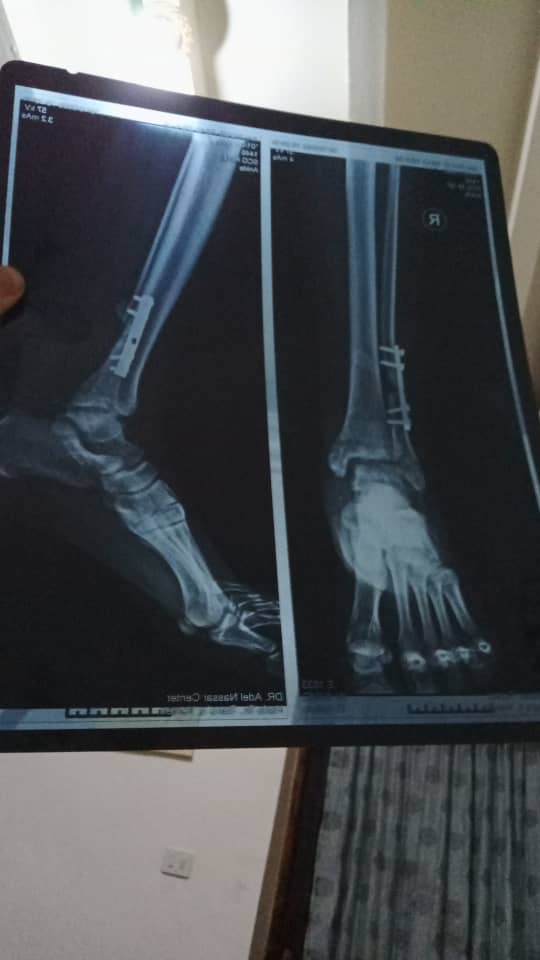

حادث مروري بثلاث كسور في الرجلين

حصل لي كسر مضاعف في قصبة الرجل وكسر في عظمة الشزجيه وتماجراء عمليه وتركيب مسمار نخاع وتجبيس الرجل للكسر الاخر...